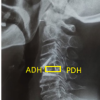

The donor had undergone a 3-level ACDF procedure to fuse levels C4-C7 at some point in his lifetime for an unknown reason. As the procedure appears to have been successful, there are a few interesting anatomical findings to consider. First, there is an aberrant left VA (LVA) originating from the subclavian artery at the level of T1/T2. The LVA takes a slightly medial course before entering the transverse foramen at C5, an unusual high entrance level (Fig. 1). Second, there is an absence of left anterior tubercles at the levels of C5 and C6 with prominent osteophytes on the right anterior tubercles/transverse foramina. Third, the VA runs within 2 mm of the ACDF plate.

The right VA (RVA) originates from the subclavian artery at the level of C7/T1 before entering the transverse foramina of the C6 vertebrae. Therefore, the RVA has a common anatomical path (Fig. 1-3, Table 1).